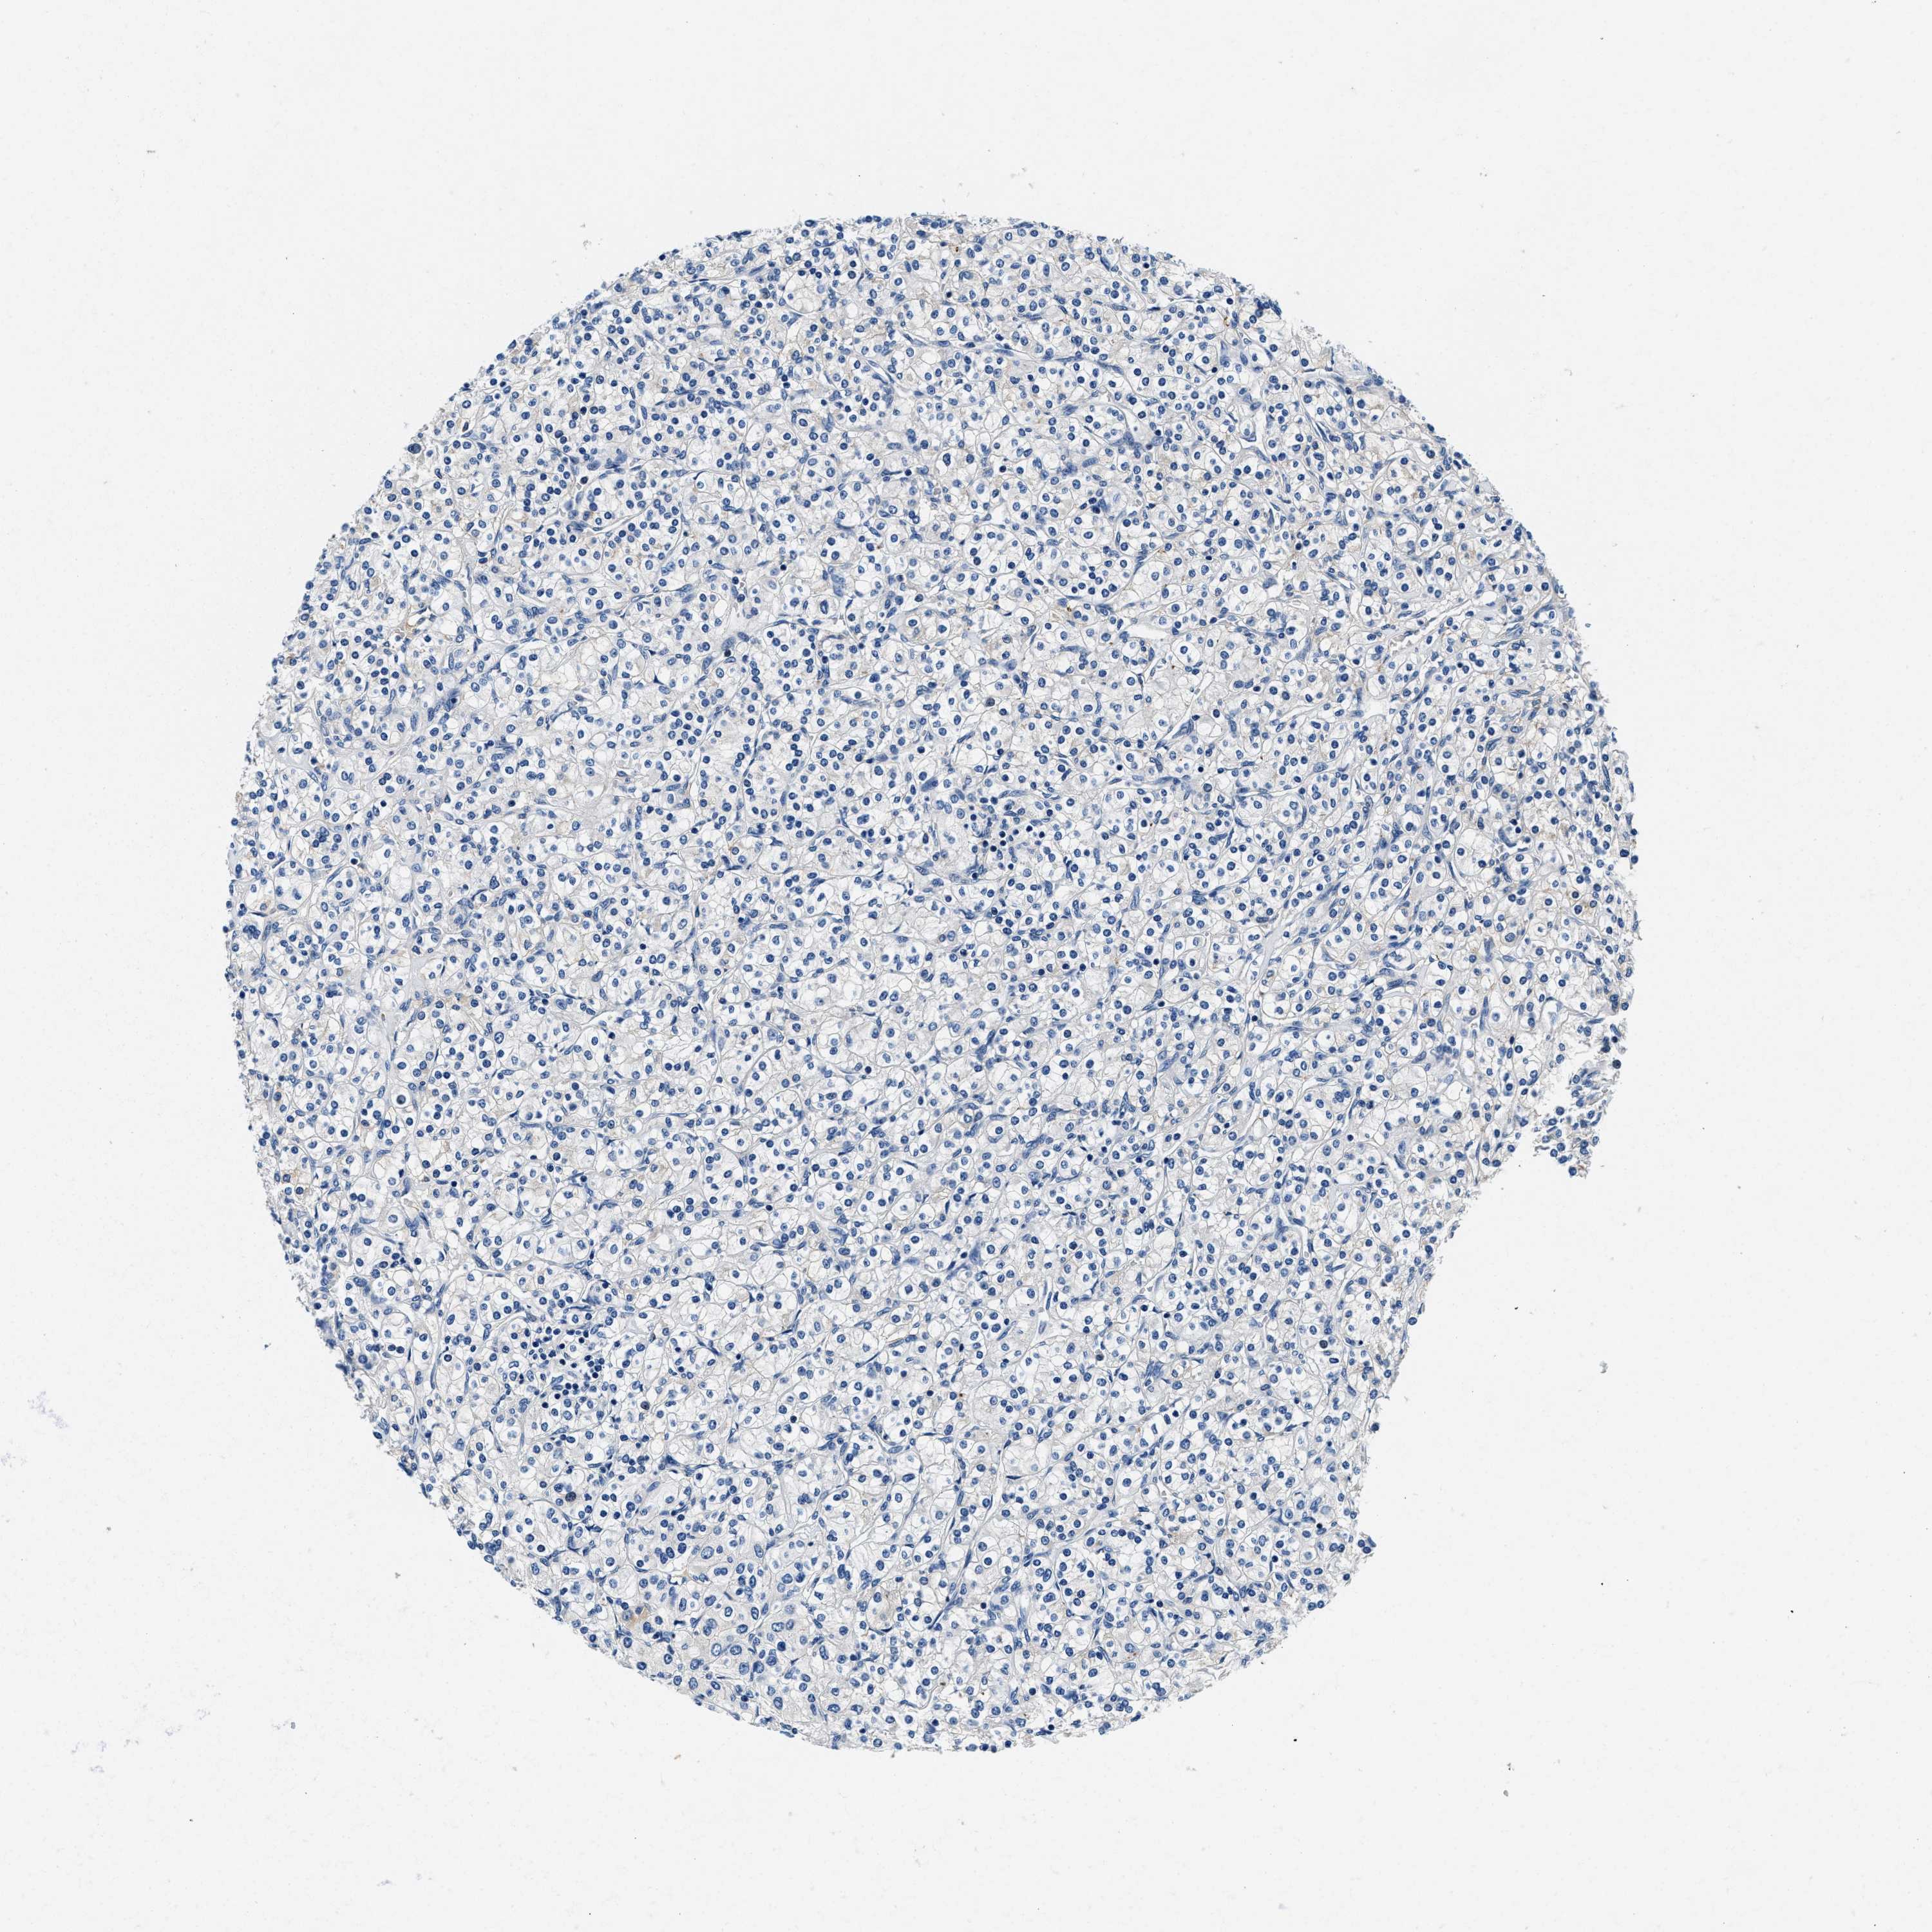

KIDNEY RENAL PAPILLARY CELL CARCINOMA (TCGA) - Interactive survival scatter ploti

The Survival Scatter plot shows the clinical status (i.e. dead or alive) for all individuals in the patient cohort, based on the same data that underlies the corresponding Kaplan-Meier plots. Patients that are alive at last time for follow-up are shown in blue and patients who have died during the study are shown in red.

ZFAND3 is not prognostic in Kidney Renal Papillary Cell Carcinoma (TCGA)

Best expression cut offi

: 36.38